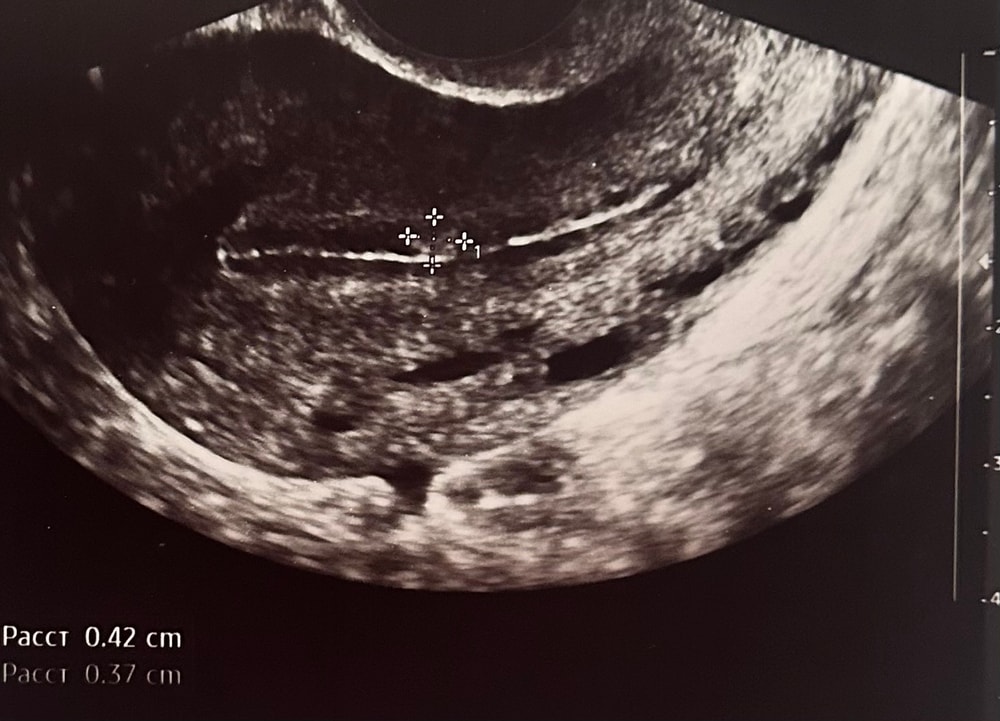

Подозрение на полип перед крио

было ли у вас подозрение на полип? Может был похожий случай как у меня на узи?

(Прикрепляю фото полипа на узи)

На фото полип классический. Гистероскопия вам в помощь. Пайпель только время затянете